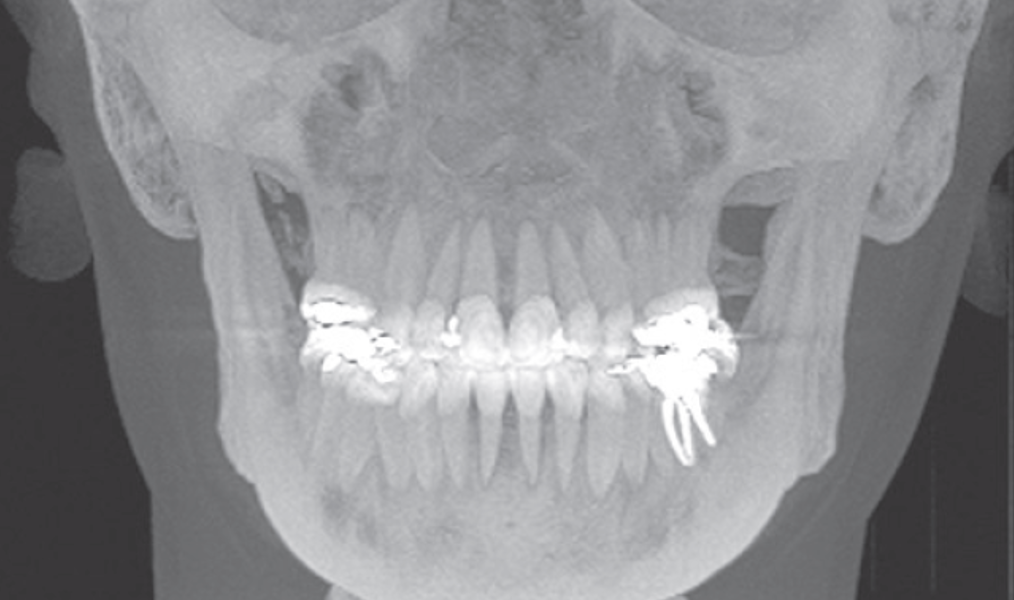

Podemos observar características anatômicas nos sentidos coronal, axial e sagital.

Assim, de uma tomografia 3D podemos fazer uma reconstrução 2D (radiografia panorâmica), uma visualização coronal de um dente com suspeita de reabsorção radicular, trinca ou até mesmo fraturas.